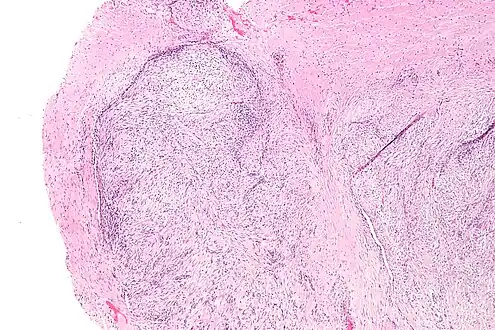

| Micrograph of nodular fasciitis showing the haphazard arrangement of cells (tissue culture-like pattern). H&E stain. | |

The microscopic histopathology of hematoxylin and eosin stained nodular fasciitis tumors (see above and three below figures) consists of spindle-shaped myofibroblastic cells (i.e. cells with features of smooth muscle cells and fibroblasts.).[9] These cells are in a myxoid (i.e. more blue or purple compared to normal connective tissue because of excessive uptake of the hematoxylin stain) or a collagenous (high content of collagen fibers) tissue background. The neoplastic myofibroblasts are arranged in whorls and/or short bundles. These cells may show high rates of replicating as judged by their mitotic index but these mitoses are normal in appearance. The tumor tissues often contain red blood cells, lymphocytes and giant osteoclast-like giant cells and may contain sites of bone-like tissue.[11] NF is sometimes classified into three subtypes based on its predominant histopathological pattern: myxoid or reactive (type I), cellular (type II), and fibrous (type III).[5] These patterns appear related to the duration of the lesion with the myxoid variant tending to have the shortest duration and the cellular and fibrous variants tending to have progressively longer durations.[15]Immunohistochemical analyses indicate that the cells in NF usually express smooth muscle actin, muscle specific actin, and vimentin proteins but generally do not express CD34, S-100 protein, desmin, trypsin, factor VIII, F4/80 (also termed macrophage-specific antigen), or HLA-DR1 proteins.[11] Uncommonly, the cells in NF tumors also express the CD68 (a histiocyte-specific marker) protein.[5]